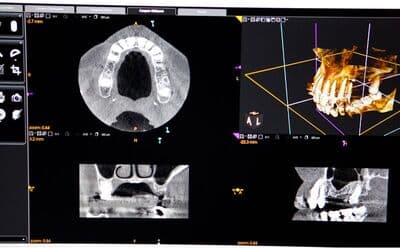

CT

3次元的に頭蓋骨の解剖学的形態を詳細に把握することで、インプラントの手術をより安全に行うための診断ツールです。現在、インプラント治療ではCT撮影は必須とされています。

ガイデットサージェリー

CT画像とお口の中をスキャニングしたデータをマッチングさせ、インプラントを正確な位置・角度・深さに埋入する補助器具のことです。難しい位置でのインプラントの埋入でもガイドを用いることで、安全に治療を遂行することができます。